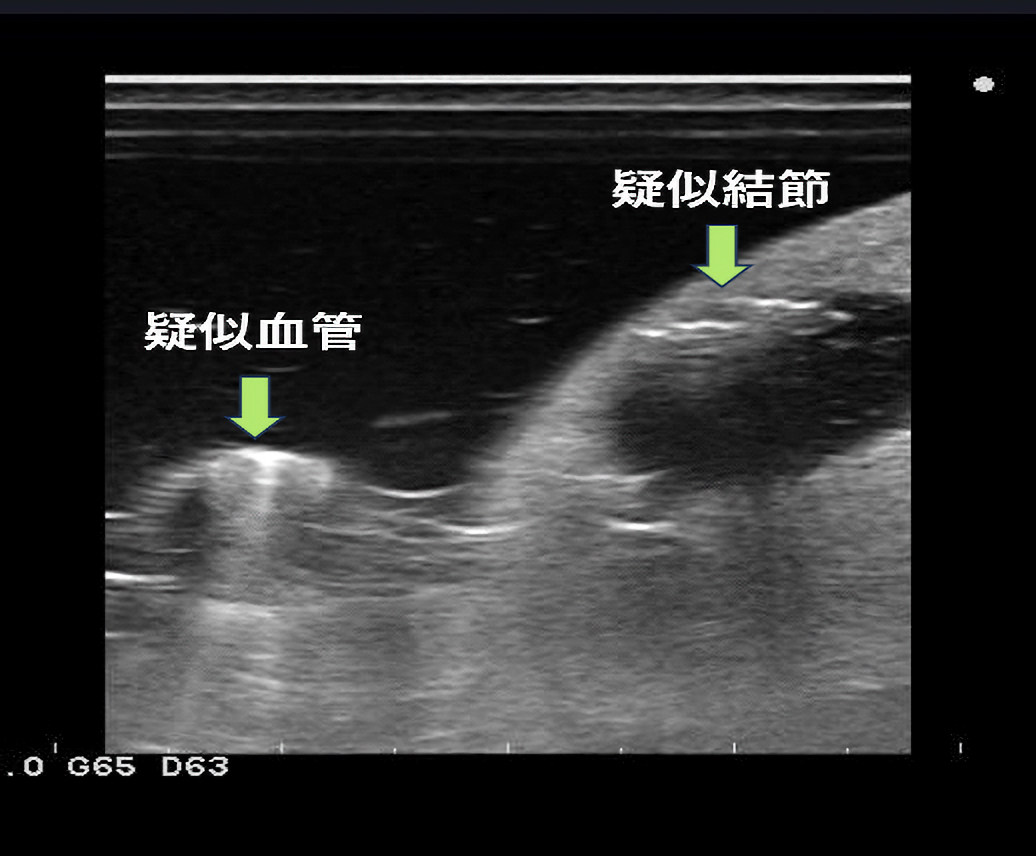

作製したモデルは、超音波下で腎臓の皮質・髄質に該当する部分のコントラストは実際の腎臓のものに類似しており、針穿刺の際にモデル内に針が侵入する様子が超音波下で観察可能です。本モデルの検証のため、岡山大学病院の腎生検経験20例未満の研修生10名に腎生検模擬を実施し、腎生検経験20例以上の腎生検に熟達した腎臓内科医20名がその様子を観察あるいは模擬を実施しました。また、腎生検模擬後に全参加者にアンケート調査を実施しました。その結果、90%の研修生が今回の腎生検模擬によって患者への腎生検に対する不安が軽減されると回答しました。

作製したモデルは、超音波下で腎臓の皮質・髄質に該当する部分のコントラストは実際の腎臓のものに類似しており、針穿刺の際にモデル内に針が侵入する様子が超音波下で観察可能です。本モデルの検証のため、岡山大学病院の腎生検経験20例未満の研修生10名に腎生検模擬を実施し、腎生検経験20例以上の腎生検に熟達した腎臓内科医20名がその様子を観察あるいは模擬を実施しました。また、腎生検模擬後に全参加者にアンケート調査を実施しました。その結果、90%の研修生が今回の腎生検模擬によって患者への腎生検に対する不安が軽減されると回答しました。

軟質エラストマー成型品/甲状腺穿刺シミュレーター (製品名:せんしろう)